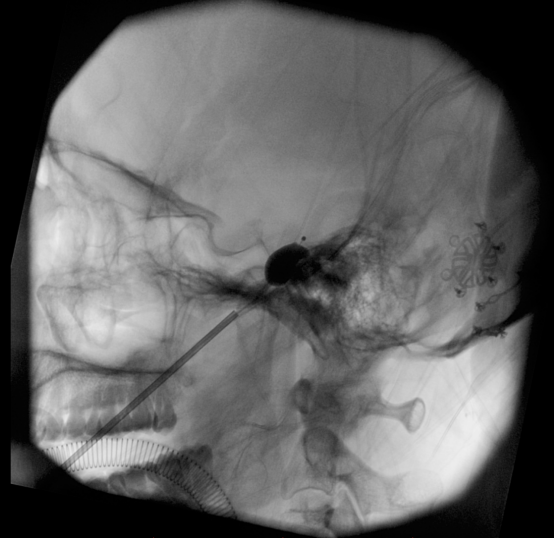

但由于刘女士是个爱美人士,要求面部不能有疤痕,为此杜主任改良了既往的三叉神经微球囊压迫手术的穿刺点,把穿刺点由原来嘴角外侧面部改为口腔内粘膜,达到患者面部不留疤效果,虽然增加了手术操作难度,经过杜昌旺主任团队术中努力,成功为刘女士实施了经口腔内穿刺三叉神经半月节微球囊压迫术,如下图

术后即刻刘女士面部疼痛消失,说话吃饭恢复正常,术后1天刘女士就康复出院。值得一提的是,与传统手术不同,本次手术经口腔内穿刺,面部完全看不到任何痕迹。“就像没做过手术一样!”刘女士对着镜子笑了——解决三叉神经痛,没有红肿,没有疤痕,只有久违的轻松。“想不到日夜疼痛的恶梦,一个球囊就搞定了”。刘女士笑言。

该微创治疗三叉神经痛的方法是在影像学引导下,将球囊导管经面部皮肤穿刺至颅内三叉神经半月节所在的 Meckel腔,注入造影对比剂使球囊充盈,压迫三叉神经半月节,损伤传导痛觉的神经,从而达到缓解疼痛的目的。这项技术优势在于:创伤小,费用低,可重复,操作可视化,住院时间短。